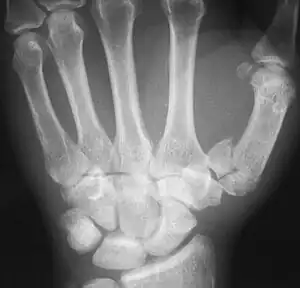

Rolando fracture - a comminuted intra-articular fracture of the first metacarpal bone.

The cause is generally a force along the long axis of the thumb, such as during a fight.[3][4] Diagnosis is by medical imaging; such as X-ray, CT scan, or MRI.[3] It results in at least three bone fragments, which often form a T- or Y-shaped pattern.[3][4] It differs from a Bennett fracture which only results in two bone fragments.[4]